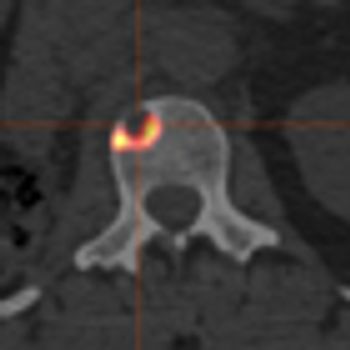

The ALSYMPCA phase III clinical trial, recently published, demonstrated that radium-223 dichloride was well-tolerated and resulted in an improvement in overall survival by 3.6 months compared with placebo.